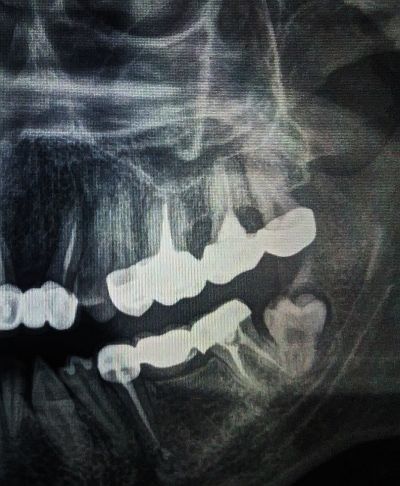

d__d написа:Здравейте! Имам един проблем, който вече продължава няколко месеца. Януари месец прекарах вирусна инфекция и след това много често имам болки в гърлото, сухота, дразнене, които отшумяват и се появяват. Имам едни бели налепчета- по- точно изглеждат като малки , ситни млечно бели точици (7,8 на брои), разположени по лявата дъга на гърлото. Пусках два пъти гърлен секрет. Нищо не показва, чисто е- няма бактерии, няма гъбички. От нищо не се повлияват. Посетих УНГ, според него нямам проблем и ме насочи към стоматолог, тъй като забеляза, че от същата страна имам мъдрец, който расте накриво (посока към бузата). Освен това до него имам пломбиран зъб, който веднага след като ми сложиха пломбата стана много чувствителен. Въпросът ми е- дали тези налепчета е възможно да са от зъбите? Притеснявам се да извадя мъдреца, за да не се разрасне тази инфекция на гърлото. Възможно ли е да е рак!? Имам зъбен камък в момента за махане, както и едно червено петънце на венеца на предните зъби, когато ходих на стоматолог, каза, че кърви като го пипне, и е възможно да е от зъбния камък и леко възпалените венци. Правила съм снимка на всички зъби, нямаше по снимката нещо за притеснение, според стоматолога. Все още не съм посещавала стоматолог във връзка с белите налепчета, предстои ми консултация.